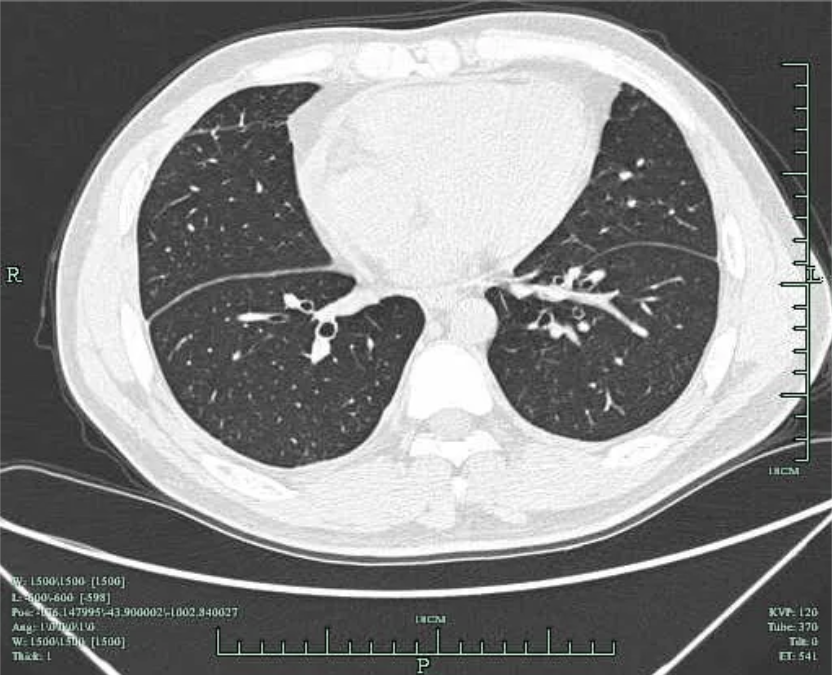

患者3周(2022年10月10日)前出现左前胸及侧胸疼痛,呈阵发性隐痛,能忍受,疼痛无放射性,否认疼痛时黑曚、汗出、否认畏寒发热等,社区医院用药(具体药名不详)后好转;1周前(10月23日)左侧胸部出现压榨痛,疼痛呈持续性不能缓解,伴胸闷气急,至县医院就诊:血常规:白细胞 11*10^9/L(3.5-9.5*10^9/L),血红蛋白及血小板正常;超敏C反应蛋白:67.95mg/L(0.00-3.30mg/L),心电图示:V2-V5导联ST段凹面向上稍抬高(图1);10月24日肺部CT示(图2):左肺散在炎症,左侧胸腔少量积液伴邻近肺组织膨胀不全,两肺散在纤维灶,心包积液,升主动脉增宽;10月24日心超示:三尖瓣反流,左室舒张功能减低,心包积液(心尖部心包分离约0.5cm),心动过速,EF:57%。

图2 肺部CT 肺窗提示 右侧胸腔积液,左侧胸腔积液引流后改变